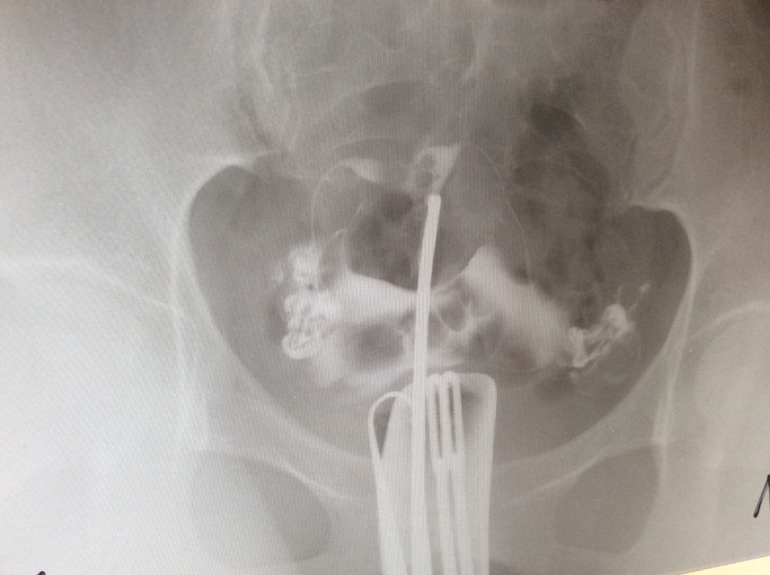

Здравствуйте! Мне 28. Планируем 2 года, анализы все хорошие,включая СГ. Отправили на гсг, трубы проходимы, но нашли подозрение на полипы на теле матки. УЗИ их не видит. Подскажите видите ли Вы их на этих снимках. Мне назначена стимуляция с 5 ДЦ. Вот я и думаю делать или искать полип дальше?! Заранее спасибо!

Здравствуйте! Скорее всего подозрение на полипы полости матки возникли из-за 2-х округлых дефектов на снимках, они отчетливо видны на 2 и 3 снимке, хотя это могут быть и пузырьки воздуха. Для исключения внутриматочной патологии необходима диагностическая гистероскопия (возможно, офисная)